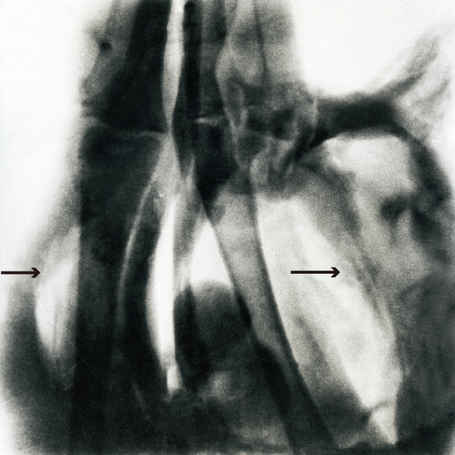

弹丸等高速投射物击中机体后,机体内瞬间形成急剧胀缩的空腔现象及所产生的致伤效应。5.56毫米枪弹击中狗后肢后1.616毫秒时的高速X射线照片  高速投射物侵彻机体时,产生很强的压力波(最高压力可达10兆帕以上)作用于原发伤道周围的软组织,迫使其向外急剧扩张,形成巨大空腔。空腔的最大直径可达投射物...